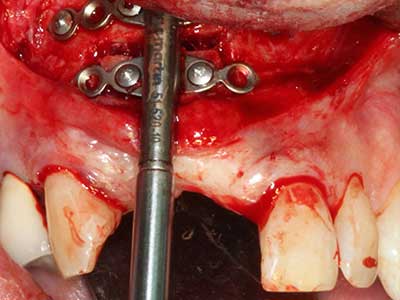

Когато се извършват хирургични процедури върху кост в непосредствена близост до чувствителни структури като кръвоносни съдове или нерви, ротиращите инструменти създават значителен риск за ятрогенно нараняване. Пиезоелектрическите апарати могат да бъдат от помощ при препарация на костно покритие и отстраняване на твърда кост близо до нерви, особено за оголване на нервите след ятрогенно нараняване, както и по време на латерализация на нервите за резекционни и реконструктивни процедури или поставяне на имплант (Фиг. 17-20). Лекият контакт между пиезонакрайника и нерва по принцип не води до нараняване, но ако действате непредпазливо с трионообразни движения или приставки за остатъчен костен субстрат, може да причините временно или перманентно увреждане на нерва. Въпреки това, рискът от увреждане се счита за много по-малък, отколкото при употреба на триони или ротиращи инструменти (Pereira, Gealh et al. 2014).